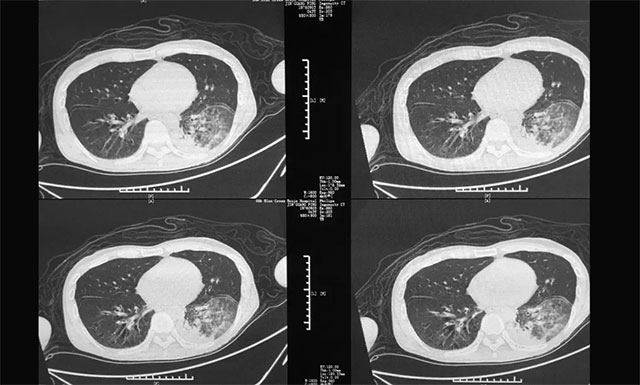

▲ 患者出現(xiàn)多種并發(fā)癥:肺部感染嚴(yán)重

入院后,潘仁龍團(tuán)隊對陳先生進(jìn)行了全面仔細(xì)的檢查,根據(jù)其各項檢查結(jié)果、目前出現(xiàn)的癥狀,并結(jié)合其20余年的飲酒和吸煙史以及外院診治情況,陳先生最終被確診為:1、使用酒精引起的戒斷狀態(tài)伴有譫妄;2、慢性酒精中毒;3、肺部感染;4、液氣胸;5、大皰性肺氣腫。